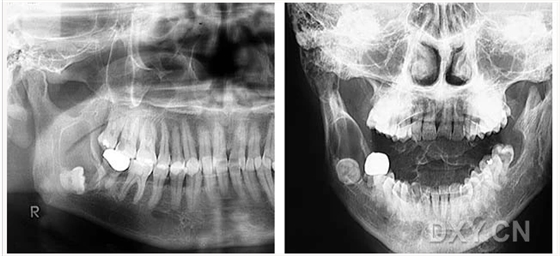

牙源性鈣化囊腫

牙瘤!

牙源性鈣化囊腫    牙瘤!